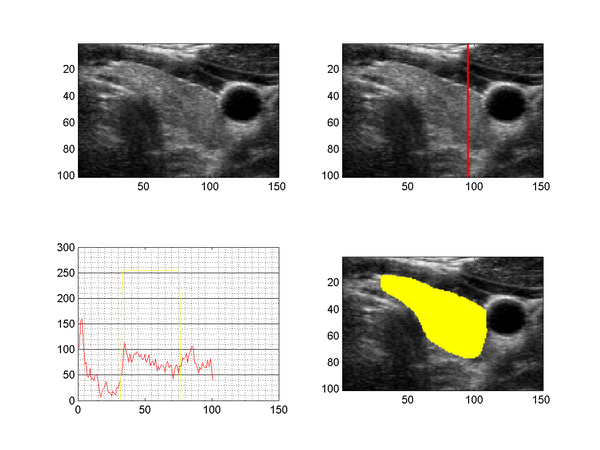

Bias Field on Ultrasound Image and Segmentation of the Thyroid

The figure above shows a slice taken from a 3D ultrasound image of the human thyroid (upper left), together with the intensity profile along a line through the tyhroid (upper right, lower left) and a segmentation (lower right). US images suffer from speckle noise, sonic attenuation and also regions of sound shadows (insufficient gel layer). The sonic attenuation cannot be fully compensated by the imaging devices and the effect is clearly visible when examining the intensity profile along a line through the thyroid region (lower left image), which shows decreasing intensities with increasing distance to the surface.